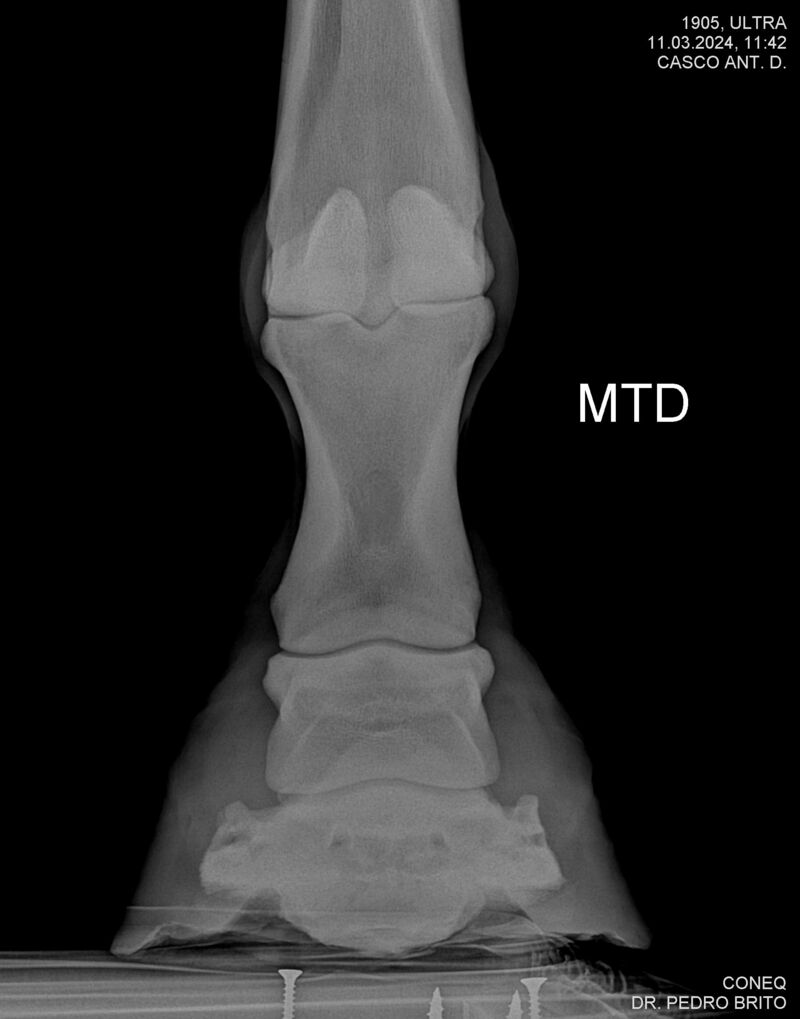

ULTRA DO CACH